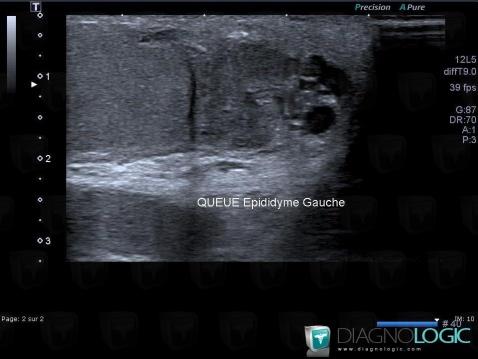

épididymite, Scrotum, Echographie

Voici les informations spécifiques à l'image clé ci dessus:

- Diagnostic épididymite, Localisation(s) Scrotum, comportant les gammes Lésion épididymaire